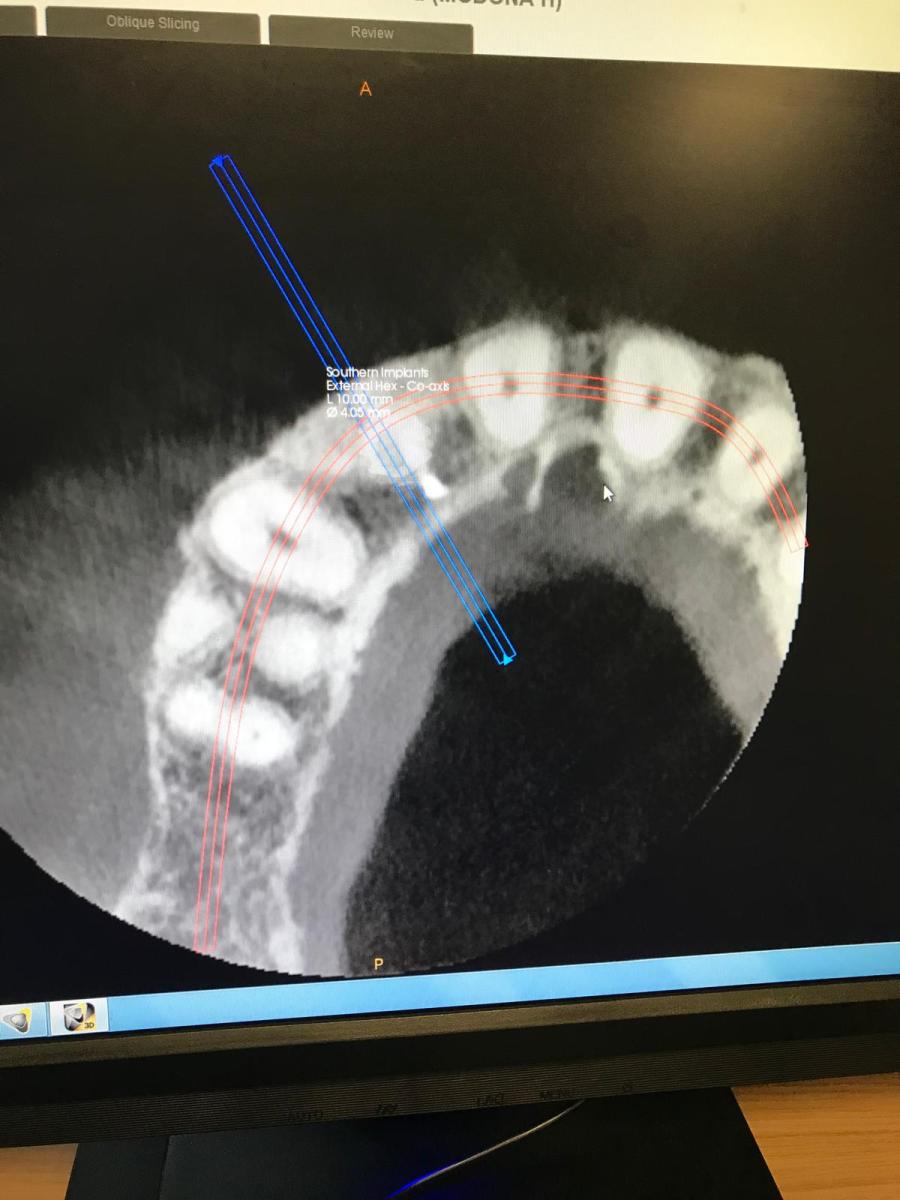

Single implant case in the anterior region, following digital planning to ensure precise positioning and optimal aesthetic outcome. Pre-operative CBCT analysis was used to assess bone volume and guide implant angulation, allowing for a prosthetically driven approach.